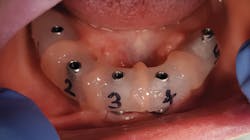

When taking an impression of the multiunit abutment, I use the direct pickup coping from BioHorizons (figure 3). This has been the easiest and most predictable impression I have found. The setup for taking these impressions is very simple and made easy with the MiraTray implant tray from Hager Worldwide (figure 4). What I like about the MiraTray is that I can see through the material as I try in the trays to ensure the proper size is used.

I seat the direct pickup copings hand-tight onto the multiunit abutment, syringe a light-body polyvinyl siloxane (PVS) around the coping, and then fill the MiraTray with medium or heavy-body PVS as well (figure 5). Seating the MiraTray is what makes it indispensable in the full-arch impression. The long screws of the direct pickup coping poke through the material on the tray, allowing easy access for the screw while keeping the material confined (figure 6). The tray is kept in place as the impression material sets up. Once it is ready, each of the copings must be unscrewed until the impression is released from the multiunits.